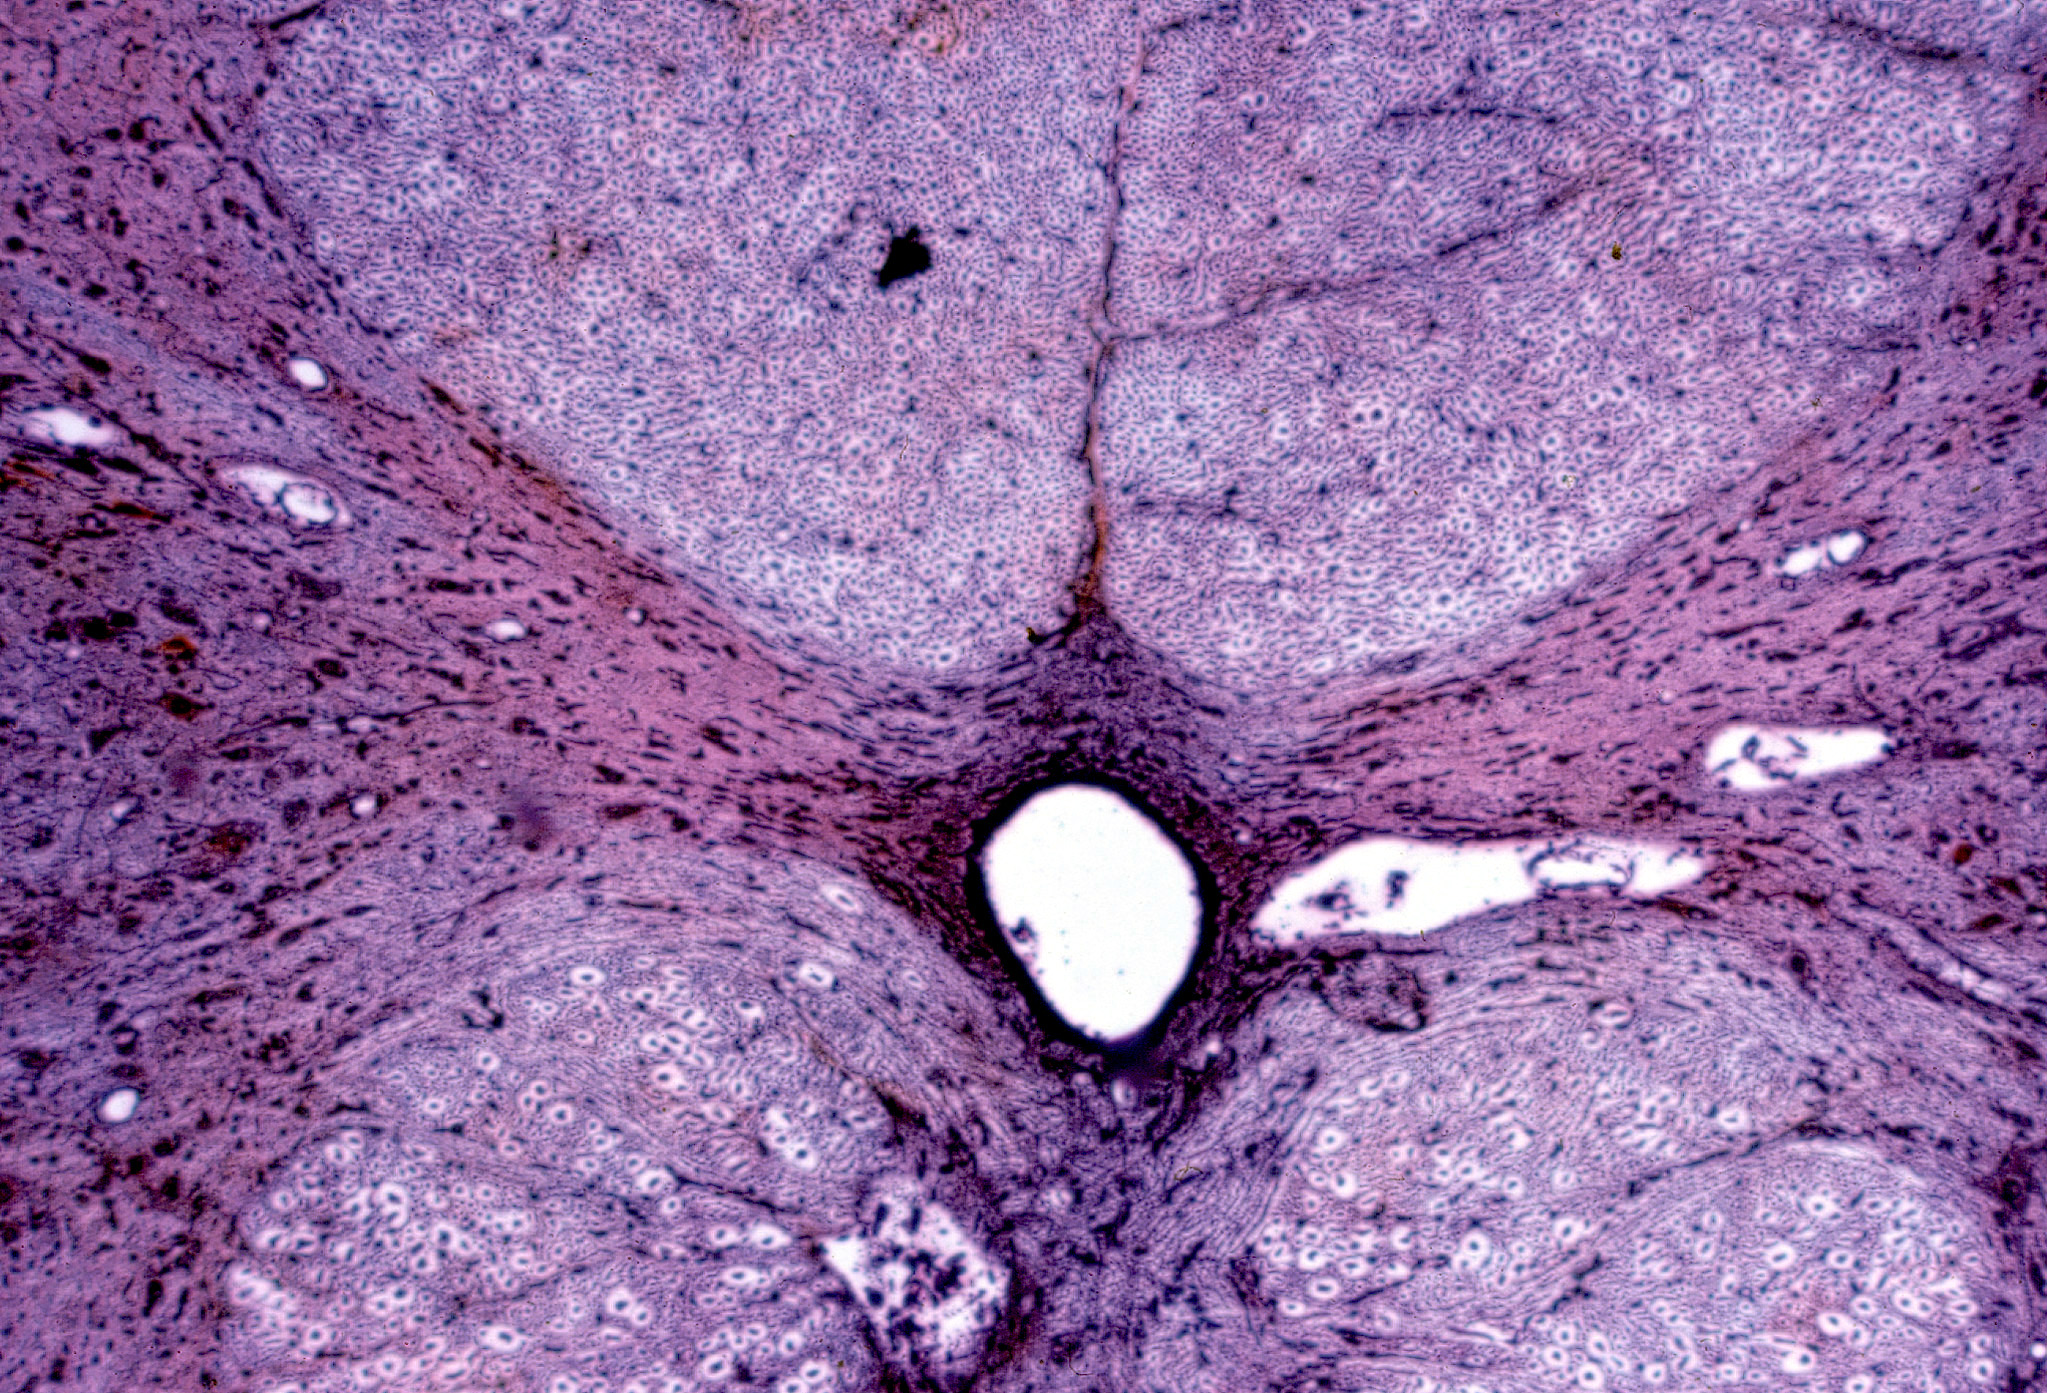

Corte de médula